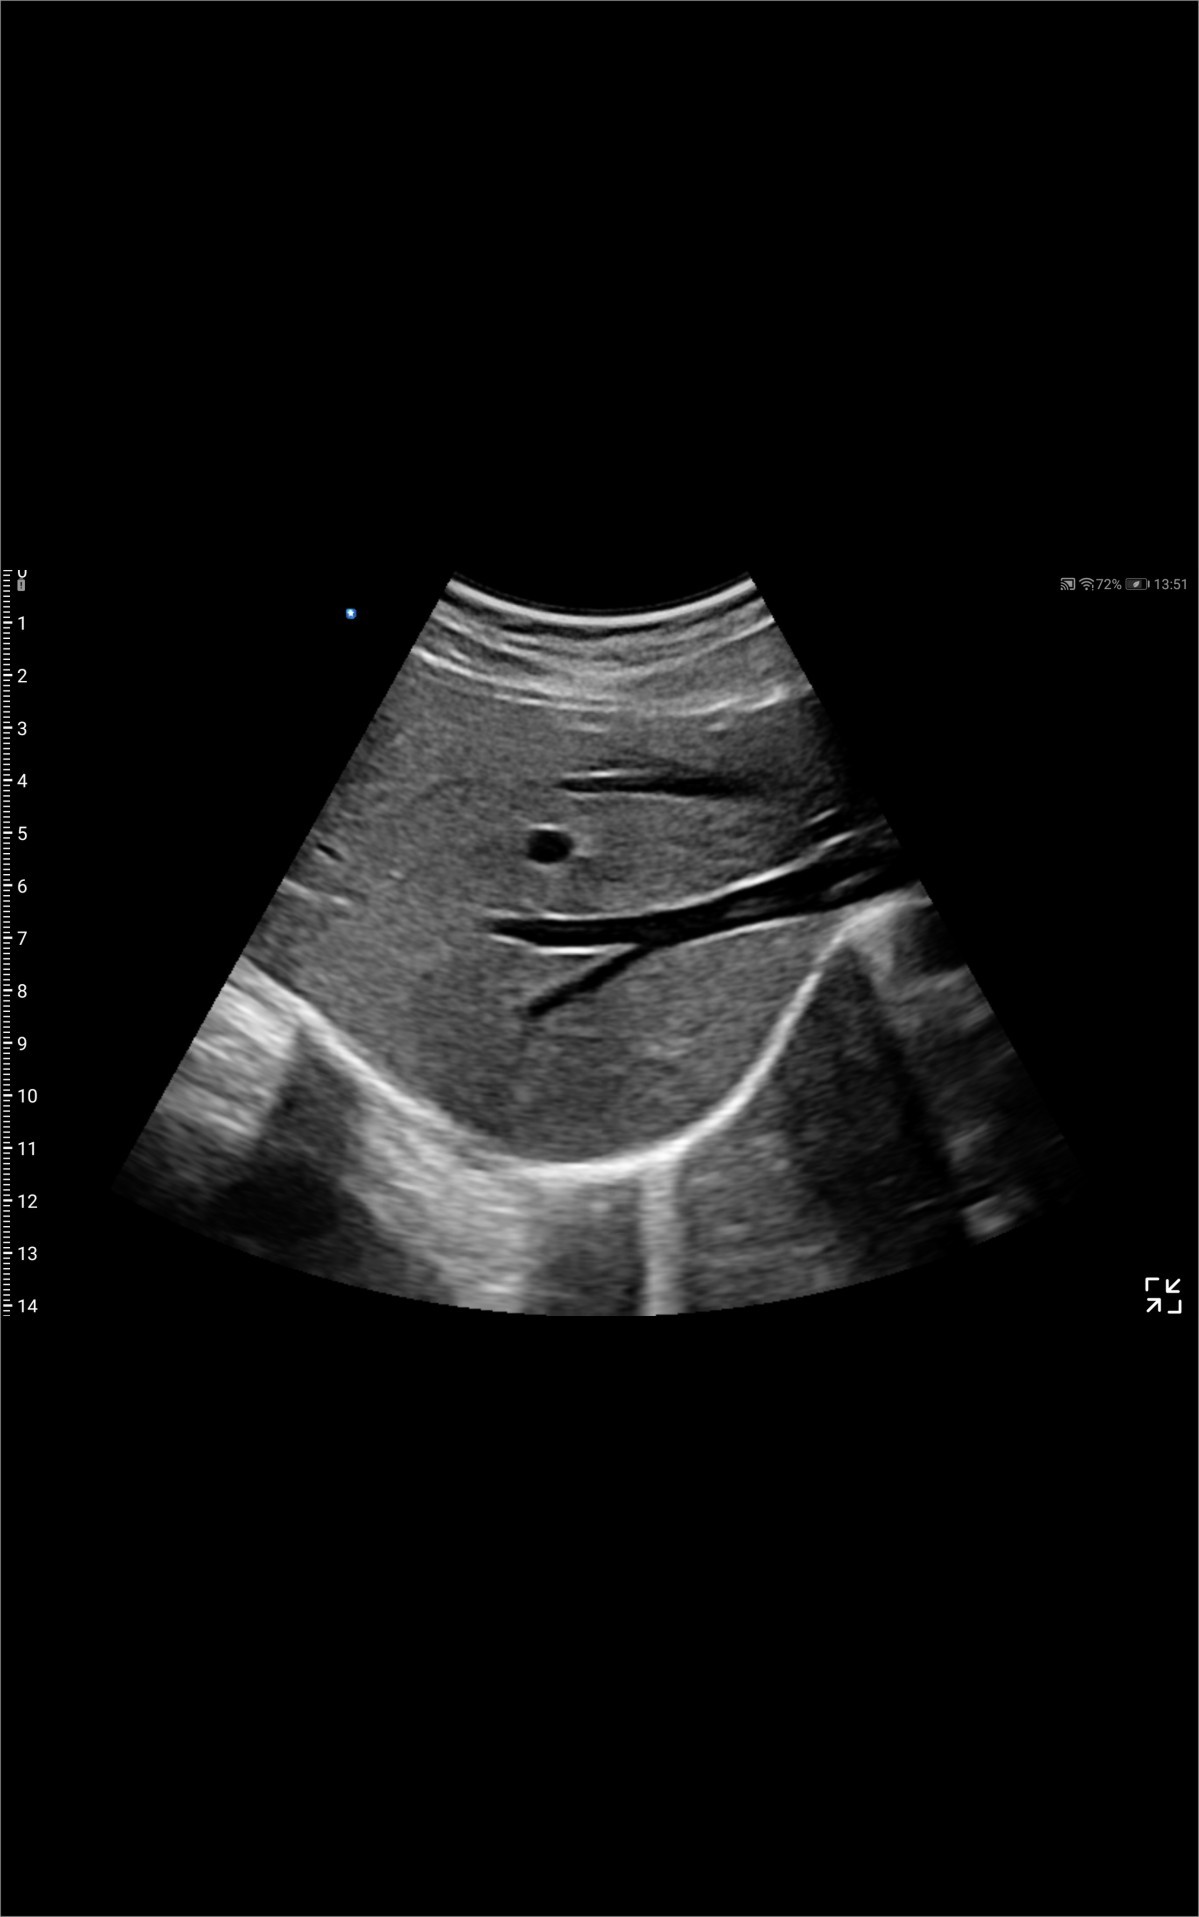

Galería de demostración

|